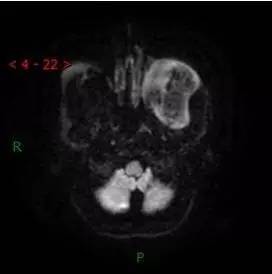

DWI